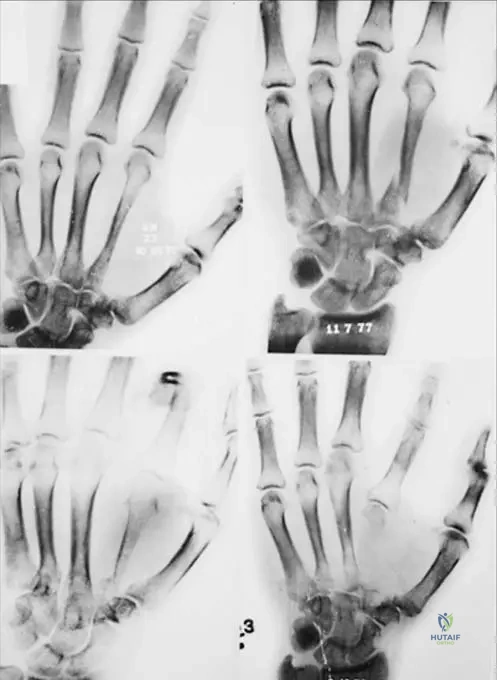

A 13-year-old male presents with an incidental finding of a nonossifying fibroma. The provided image, Fig. 11.16a, shows a characteristic location for these lesions. Which specific bone and region is depicted in Fig. 11.16a?

View Answer & Explanation

Correct Answer: C

Rationale: The image caption explicitly states, "Fig. 11.16 a–c These lesions are usually eccentric and metaphyseal, often occurring in the long bones of the lower extremity, including the distal femur (a) and distal (b) and proximal (c) tibia." Therefore, Fig. 11.16a depicts the distal femur.

Question 71

A 16-year-old female is diagnosed with an asymptomatic nonossifying fibroma. The provided image, Fig. 11.16b, illustrates another common location for these lesions. Which specific bone and region is depicted in Fig. 11.16b?

Correct Answer: B

Rationale: The image caption explicitly states, "Fig. 11.16 a–c These lesions are usually eccentric and metaphyseal, often occurring in the long bones of the lower extremity, including the distal femur (a) and distal (b) and proximal (c) tibia." Therefore, Fig. 11.16b depicts the distal tibia.

Question 72

A 10-year-old male presents with an incidental finding of a nonossifying fibroma. The provided image, Fig. 11.16c, demonstrates a third common location for these lesions. Which specific bone and region is depicted in Fig. 11.16c?

Rationale: The image caption explicitly states, "Fig. 11.16 a–c These lesions are usually eccentric and metaphyseal, often occurring in the long bones of the lower extremity, including the distal femur (a) and distal (b) and proximal (c) tibia." Therefore, Fig. 11.16c depicts the proximal tibia.